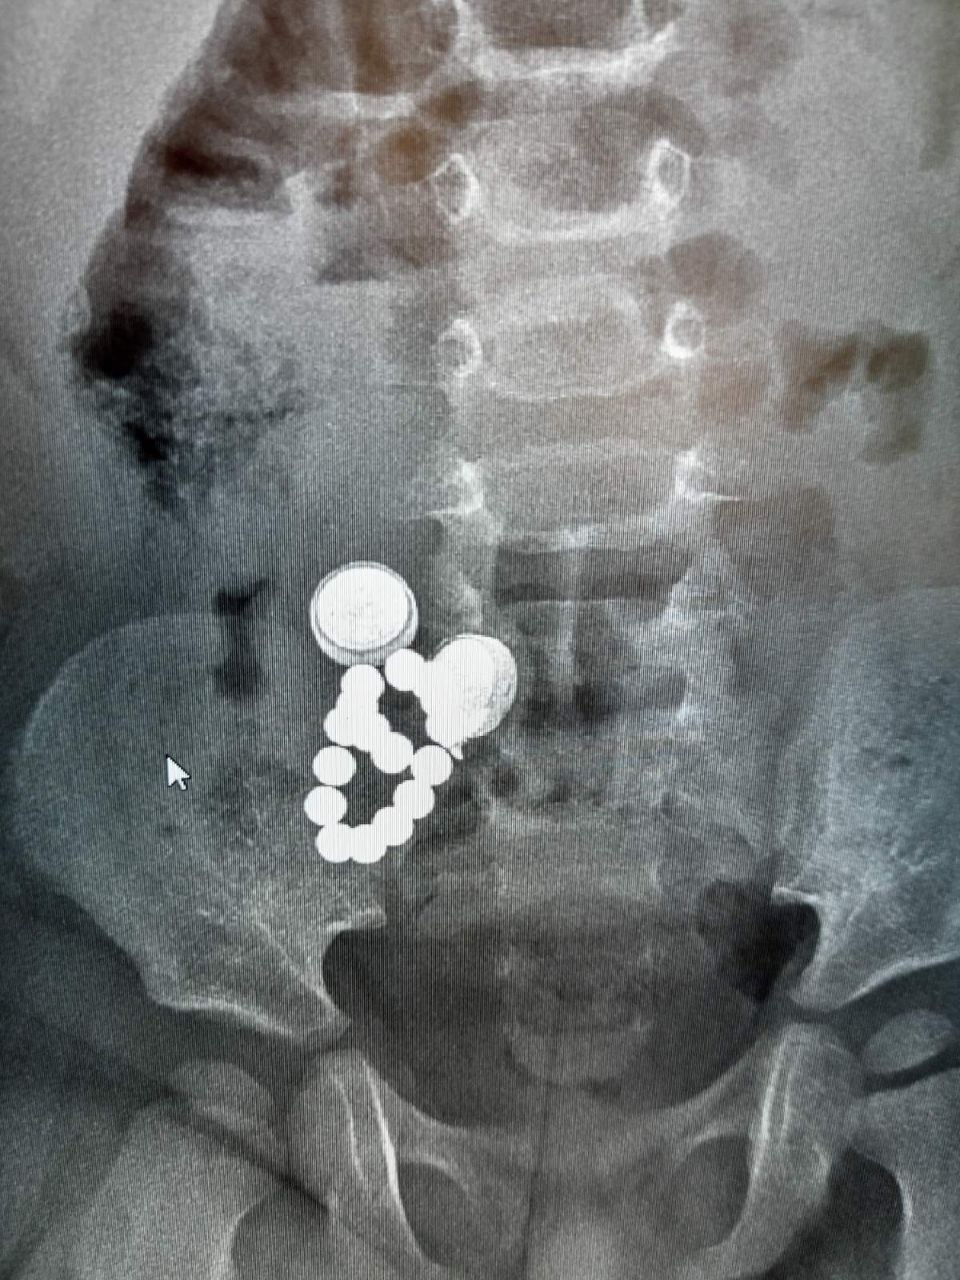

ок проглотил кольцо

Ребенок проглотил кольцо 116 фото